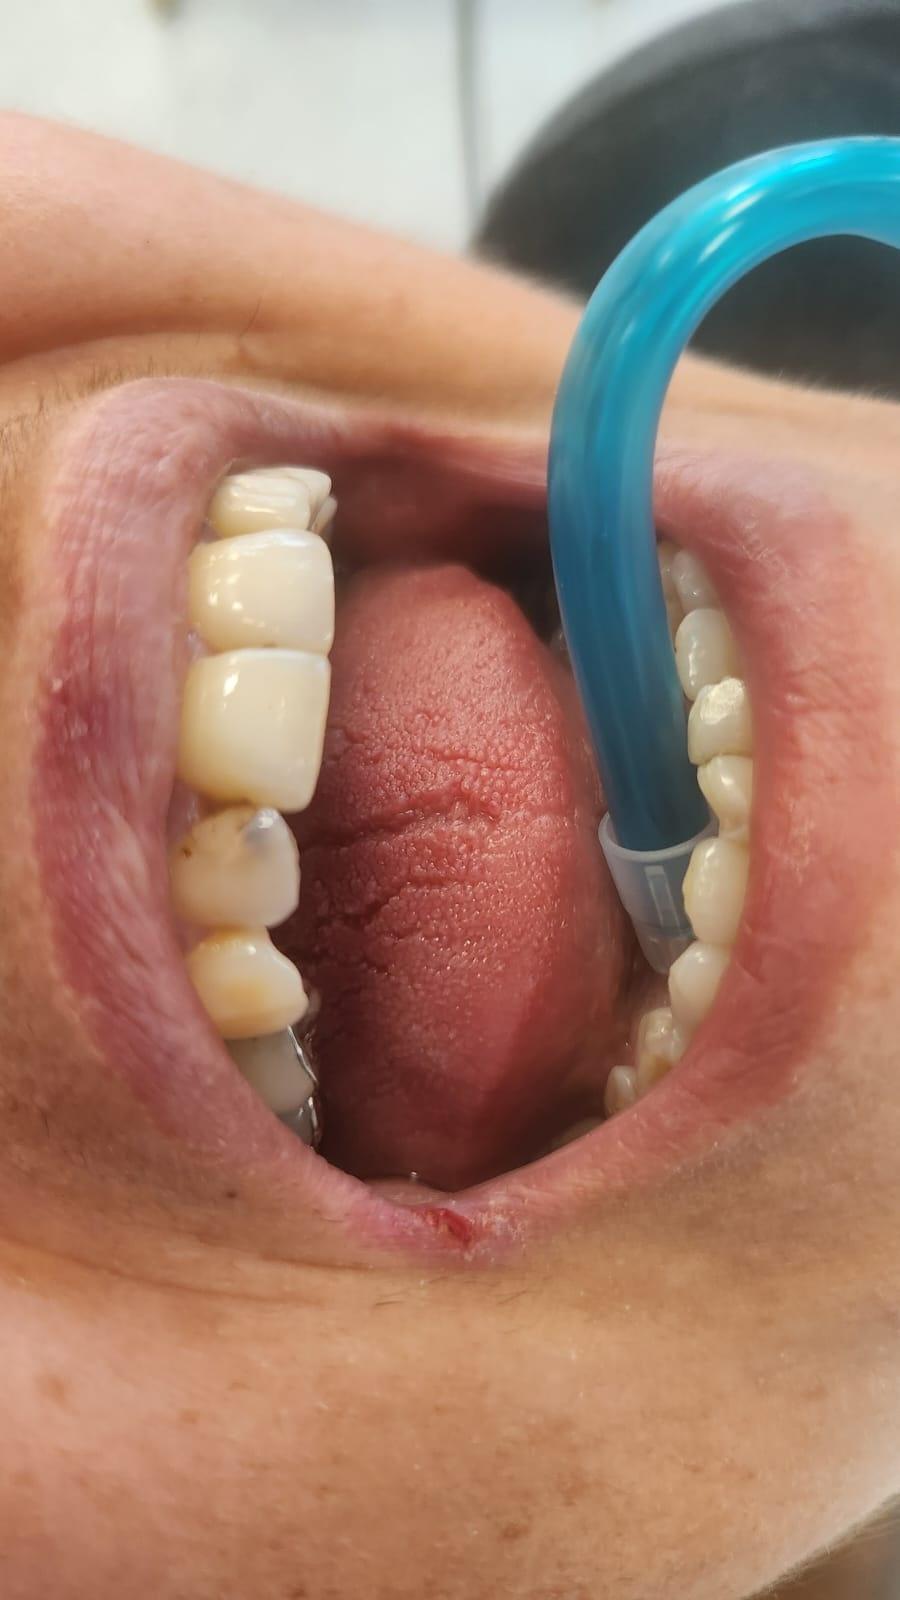

Clinica LUY ESTHETIC ART defineste parodontoza ca fiind rezultatul direct al placii dentare, care se depune pe suprafata dintilor, dar si in apropiere de marginea gingivala. Aceasta boala duce la pierderea dintilor, chiar daca ei sunt aparent sanatosi si nu prezinta carii. Edentatiile, afecteaza vorbirea, aspectul, dar si capacitatea de a mesteca.

Semnele aparitiei paradontozei:

– gingiile sangereaza la periaj;

– gingii rosii si inflamate;

– mobilitatea sau deplasarea dintilor;

– retractii gingivale cu expunerea radacinilor dentare;